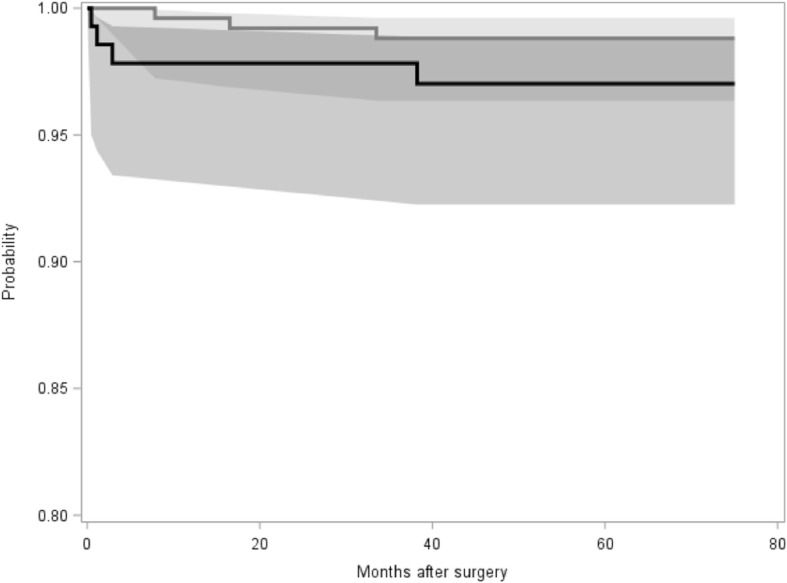

Additionally, all other reasons for stem revision were documented (Table 6). A total of 7 stem revisions had to be performed during follow-up, besides the femoral periprosthetic fractures mainly due to aseptic loosening (3 cases) and infection (1 case). In the young group, stem revision rate was 1.1%, whereas in the elderly group, 2.8% of all stems had to be revised during follow-up (p = 0.24). Survival rate (endpoint stem revision for any reason) was calculated at 60 months to be 98.81% for the young group and 97.02% for the elderly group. Log rank test revealed no significant difference between the groups (p = 0.1994) (Fig. 5).

Fig. 5.

Kaplan-Meier survival curve for the young group (grey) and the elderly group (black). Log rank test revealed no significant difference between the groups (p = 0.1994)